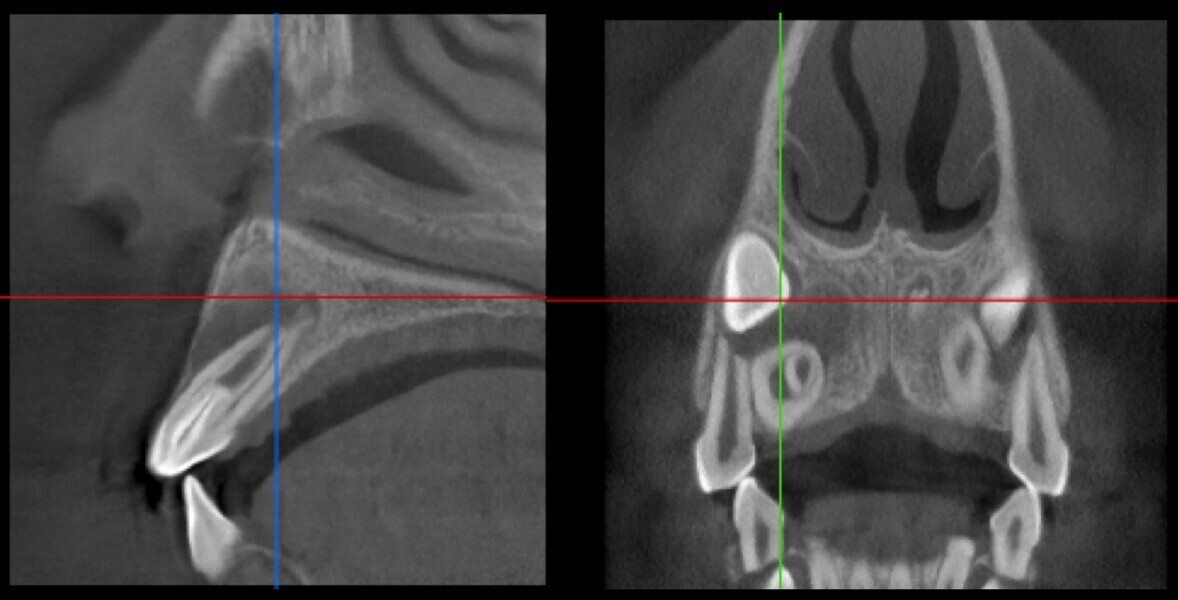

Use of 3D technology in the diagnosis and treatment of endodontic disease